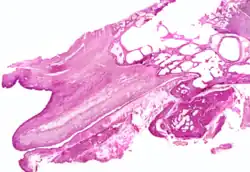

The cartilaginous part of the Eustachian tube is about 24 mm in length and is formed of a triangular plate of elastic fibrocartilage, the apex of which is attached to the margin of the medial end of the bony part of the tube, while its base lies directly under the mucous membrane of the nasal part of the pharynx, where it forms an elevation, the torus tubarius or cushion, behind the pharyngeal opening of the auditory tube.

The upper edge of the cartilage is curled upon itself, being bent laterally so as to present on transverse section the appearance of a hook; a groove or furrow is thus produced, which is open below and laterally, and this part of the canal is completed by fibrous membrane. The cartilage lies in a groove between the petrous part of the temporal bone and the great wing of the sphenoid; this groove ends opposite the middle of the medial pterygoid plate. The cartilaginous and bony portions of the tube are not in the same plane, the former inclining downward a little more than the latter. The diameter of the tube is not uniform throughout, being greatest at the pharyngeal opening, least at the junction of the bony and cartilaginous portions, and again increased toward the tympanic cavity; the narrowest part of the tube is termed the isthmus.

The position and relations of the pharyngeal opening are described with the nasal part of the pharynx. The mucous membrane of the tube is continuous in front with that of the nasal part of the pharynx, and behind with that of the tympanic cavity; it is covered with ciliated pseudostratified columnar epithelia and is thin in the osseous portion, while in the cartilaginous portion it contains many mucous glands and near the pharyngeal orifice a considerable amount of adenoid tissue, which has been named by Gerlach the tube tonsil.